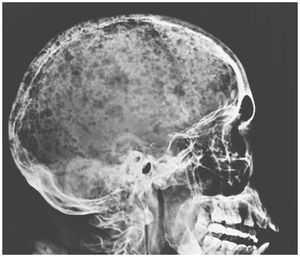

A 46-year-old man presented to the emergency department with a 1-month history of fatigue, shortness of breath, and low back pain and report of a weight loss of 30 kg over the previous 10 months. On physical examination, his conjunctiva and palms were pale. Laboratory evaluation revealed a hemoglobin level of 4.9 g per deciliter (reference range, 12 to 16), a creatinine level of 5.4 mg per deciliter (480 μmol per liter; reference range, 0.4 to 1.0 mg per deciliter [35 to 88 μmol per liter]), and a calcium level of 12 mg per deciliter (3 mmol per liter; reference range, 8.9 to 10.3 mg per deciliter [2.2 to 2.6 mmol per liter]). A skeletal survey showed diffuse osteopenia, a pubic bone fracture, and numerous radiolucent lesions on the skull, which had an appearance known as “raindrop skull” — a pattern of lytic or punched-out lesions that resemble raindrops hitting a surface and splashing. These findings are characteristic of multiple myeloma. The diagnosis was confirmed by bone marrow biopsy and aspirate samples that showed 50% clonal plasma cells in the marrow; serum protein electrophoresis revealed a monoclonal IgA paraprotein. Initial management included red-cell transfusion for treatment of anemia and hydration to correct hypercalcemia. The patient did not respond well to induction therapy and died 3 months after diagnosis. Fabio Solis, M.D. Cesar Gonzalez, M.D. Hospital General de Mexico, Mexico City, Mexico source: nejm.org